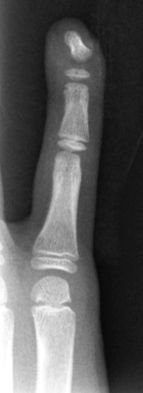

D3. Fracturas del cuello (subcondíleas)

Es una fractura extraarticular frecuente en la edad infantil y característica de lesiones por aplastamientos al cerrarse puertas de manera brusca al retirar la mano. Es más frecuente en la falange media del 2º o 5º dedo. El fragmento distal tiende a rotar a la extensión permaneciendo los ligamentos colaterales insertados en el fragmento distal.

Las fracturas no desplazadas del cuello de la falange se manejan con inmovilización con flexión de la articulación interfalángica durante 3-4 semanas. A pesar de ser fracturas alejadas de la fisis, en niños con potencial de crecimiento, menores de 8 años, se produce una buena remodelación de la fractura sin dejar secuelas cuando el desplazamiento es leve (Figura 23).

En el caso de fracturas muy desplazadas e inestables deben reducirse de manera cerrada y estabilizar con agujas cruzadas que se mantienen durante 3-4 semanas.

Se debe evitar atravesar la superficie articular con las agujas y utilizar agujas de diámetro adecuado para evitar secuelas, aunque en ocasiones es imposible sintetizarlas sin atravesar la articulación (Figura 24).

Figura 24: a- Fractura del cuello de falange media con desplazamiento posterior que requiere tratamiento quirúrgico. b- Reducción cerrada y estabilización con agujas de Kirschner.